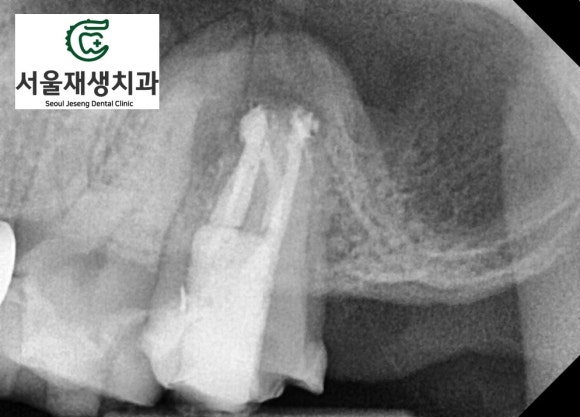

신경치료가 아주 잘된 것 같은데요...

그런데 왜 뿌리 끝 주위의

뼈가 녹아있는 걸까요?